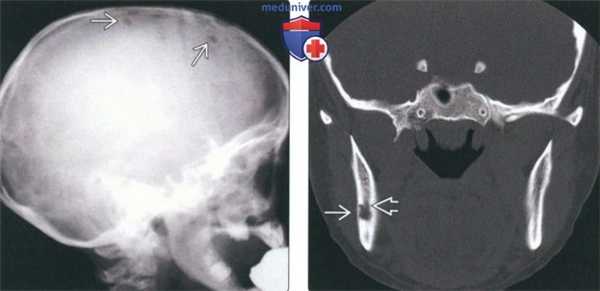

(Слева) На краниограмме в боковой проекции у ребенка с хроническим диссеминированным ЛКГ визуализируются типичные мелкие «выштампованные» просветления.

(Справа) На корональной КТ в костном окне у женщины 28 лет в ветви нижней челюсти справа визуализируются мелкие эозинофильные гранулемы с четкими контурами. Обратите внимание на истончение (но не перфорацию) щечной кортикальной пластинки. Патологический очаг, лежащий под нижнечелюстным каналом, распространяется в сторону щечной кортикальной пластинки.